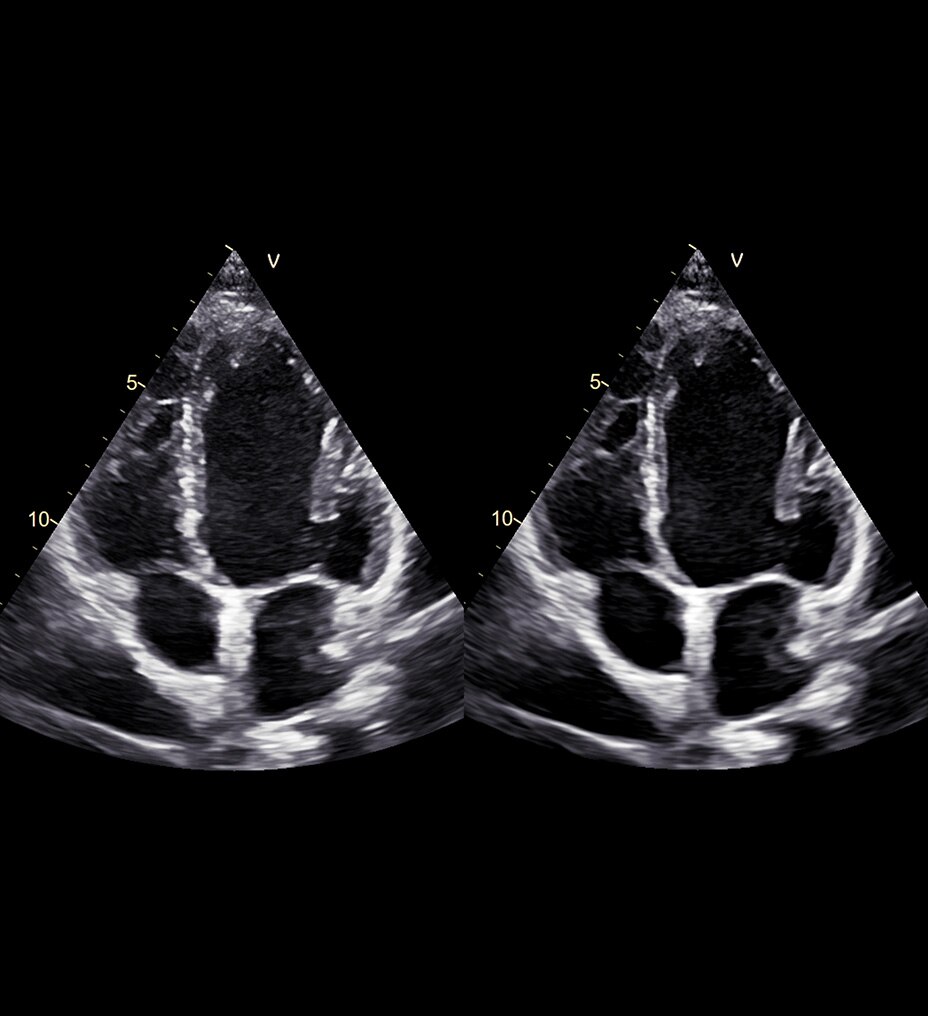

3D imaging

Expanding access to 3D imaging

Sonic DL has expanded far beyond cardiac to enable rapid 3D MR imaging in brain, spine, musculoskeletal (MSK) and body anatomies, together accounting for over 75%1 of MR exams. Effortlessly capture high-quality volumetric images of your highest-volume patient groups. Sonic DL is available in a variety of implementations, compatible with SIGNA™ 1.5T, 3T, and 7T MRI systems4 – allowing seamless workflow across healthcare facilities.